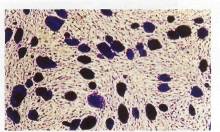

Giemsa ile boyanmış EK hücre kolonilerinin PET fiberleri arasındaki görüntüsü ( x 200).

EK hücre kolonileri giemsa ile boyandığında farklılaşmamış koloniler koyu boyanırken, farklılaşan

koloniler daha açık tonlarda boyandılar.